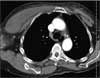

Results of a basic metabolic panel are normal except for a blood glucose level of 228 mg/dL. White blood cell count is elevated at 12,900/μL, with 80% polymorphonuclear leukocytes and 2% band forms. Creatine kinase level is 226 U/L. Ultrasonography of the breast shows diffuse edema of the upper outer quadrant of the right breast without evidence of breast abscess. Chest CT scan with contrast and T2-weighted MRI scan of the right pectoralis musculature are shown.

The CT scan of the chest shows increased subcutaneous stranding of the right breast and enlargement of the pectoralis major, with shotty axillary lymphadenopathy (Figure 1). The MRI scan demonstrates myositis of the right pectoralis with an 11 x 2-cm area of lack of enhancement, which is consistent with either necrosis or abscess within the muscle (Figure 2).

Cellulitis (choice C) can be eliminated on the basis of this patient’s history. This superficial infection of the skin with some extension into the subcutaneous tissues The CT scan of the chest shows increased subcutaneous stranding of the right breast and enlargement of the pectoralis major, with shotty axillary lymphadenopathy (Figure 1). The MRI scan demonstrates myositis of the right pectoralis with an 11 x 2-cm area of lack of enhancement, which is consistent with either necrosis or abscess within the muscle (Figure 2).